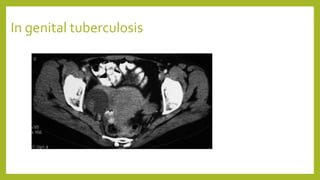

In genital tuberculosis

Investigations- ultrasound • The tubercularmass is seen as a variegated appearance with cystic and solid areas besides the uterus and may be difficult to differentiate from other tubo-ovarian masses due to a pelvic inflammatory disease or a chronic ectopic pregnancy